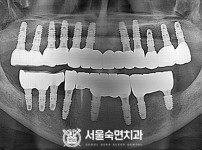

임플란트-전후사진1

치과를-선택할-때-꼭-확인하세요-서울숙면치과-임플란트-전후사진